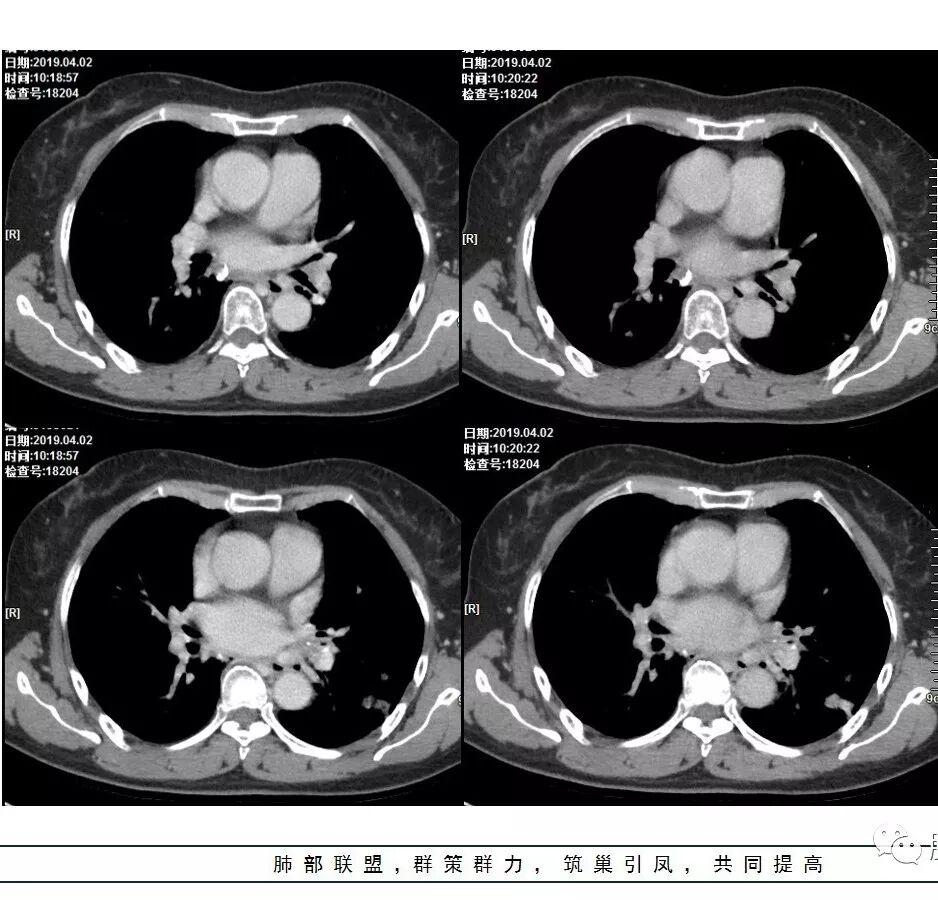

这是老问题:1、肺门区软组织密度影较弥漫;我们常规鉴别的就是结核?鳞癌?既往我们群里基本这两方向。2、弥漫的淋巴结钙化,加上马赛克灌注。马赛克灌注的原因是两个,一个是肺动脉的,一个就是小气道的问题。我们看增强的区域,没有看到栓塞,所以我倾向于小气道的问题,就是弥漫气道病变,慢性气道病变要考虑。我怀疑有没有淀粉样变性累及气道壁改变的可能。淀粉样变性是一个继发性病变,结核也可以,粉尘也可以。

今天这个病例有个明显的支气管狭窄,我倾向炎性,主要是和钙化淋巴结相关的,可能是继发的淀粉样变性。到底是什么感染,结核还是其他。我想看看复查后这个淋巴结,有没有突入到支气管腔内,如果有,他是继发于炎症的(比如中叶综合征,就是周围淋巴结压迫支气管,因为钙化淋巴结比较硬,支气管壁扛不住压力,突入支气管腔内,导致管腔狭窄,我们也称为结石征),如果没有,就和淋巴结关系不密切。之前有一例淀粉样变性的,淋巴结弥漫钙化,一种罕见的浆细胞型的CD。

4.左下叶支气管壁增厚,管腔不均匀狭窄,没有堵塞

5.肺门纵隔见增大钙化淋巴结。提示曾经存在慢性病损可能。